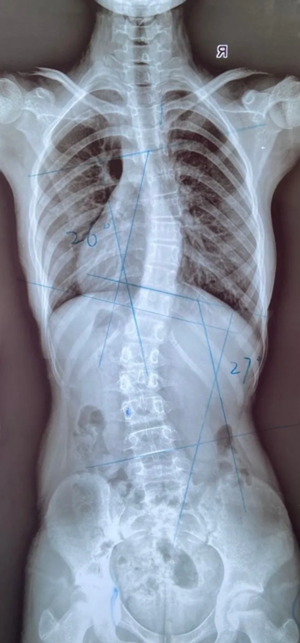

脊柱側(cè)彎的角度測(cè)量

脊柱側(cè)彎的角度測(cè)量 脊柱側(cè)彎的角度測(cè)量 脊柱側(cè)彎的角度測(cè)量...